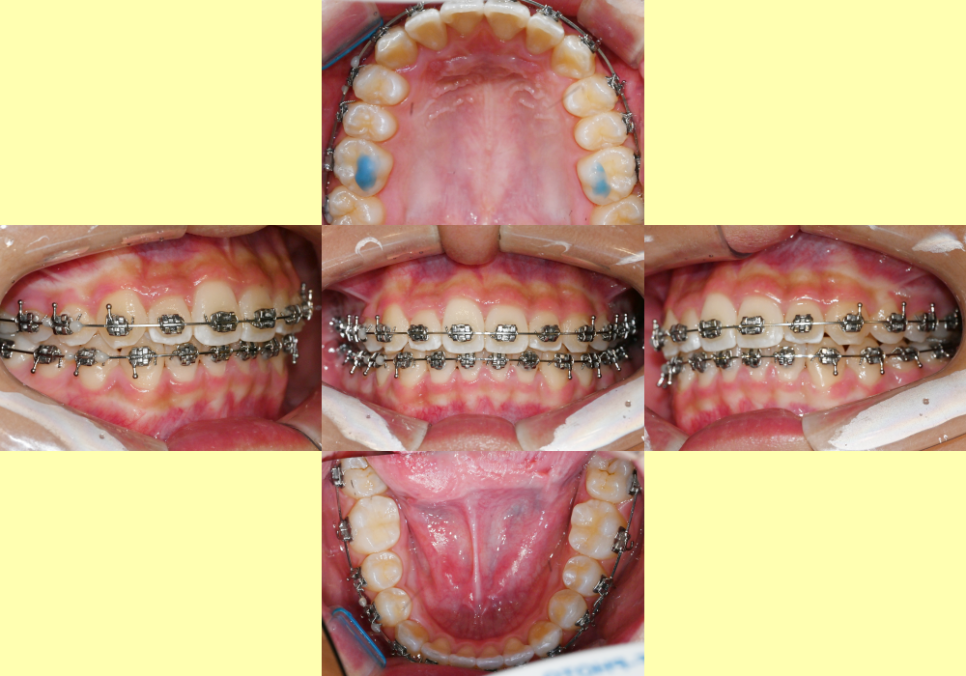

24.12.14

그 결과 기존에 틀어져 있던 앞니와

덧니가 심했던 오른쪽 측절치와 송곳니에

치열이 개선되었음을 확인할 수 있습니다.